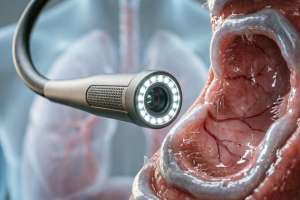

기관지경술이란 무엇입니까?

다음은 기관지경술에 관한 구조화된 백과사전 내용입니다. 귀하의 요구 사항을 엄격히 따르십시오.단락 1: 개요기관지경은 기관과 기관지의 내부 구조를 관찰하는 데 사용되는 의료 기기입니다. 이는 강성 기관지경과 유연성 기